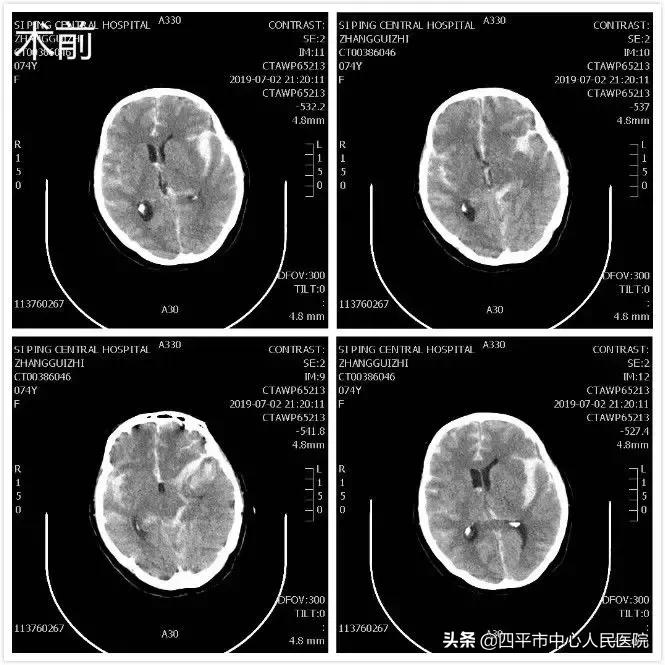

Case4 大量蛛网膜下腔出血颅内动脉瘤开颅探查术

患者张XX,于入院前2小时突发神志不清,伴恶心呕吐,呕吐物为胃内容物,四肢不动,伴尿*禁失**,无抽搐。由家属送至梨树县医院,行头CT检查提示脑出血,为求进一步治疗转送至我院,我院神经内科给予复查头CT提示大量蛛网膜下腔出血,首先颅内动脉瘤破裂所致,由于患者到我院时深度昏迷状态,呼吸微弱,HUNT-HESS分级5级,不适合行头部CTA检查及介入栓塞治疗,家属强烈要求手术治疗,请麻醉科行气管插管后入手术室,李晓东主任带领马龙急诊全麻下经左侧扩大翼点入路行右侧脑室外引流术及颅内动脉瘤探查术,术中探查患者左侧后交通动脉巨大瘤,临时阻断颈内动脉后给予确切夹闭,术中动脉瘤没再次有破裂出血。术后第1天,患者呈浅昏迷状态,刺痛可定位,四肢可自主活动。复查头部CT满意,查头部CTA见左侧后交通动脉瘤夹闭确切。但患者于术后第3天,出现迟发性脑内血肿,考虑到预后不好,家属放弃治疗出院,临出院时对我科李晓东主任及马龙医生的积极救治表示感谢。